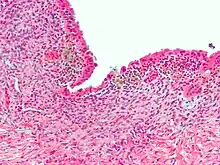

Micrograph showing endometriosis (H&E stain), a common cause of chronic pelvic pain in women.

Common causes in include: endometriosis in women, bowel adhesions, irritable bowel syndrome, and interstitial cystitis.[5][6] The cause may also be a number of poorly understood conditions that may represent abnormal psychoneuromuscular function.